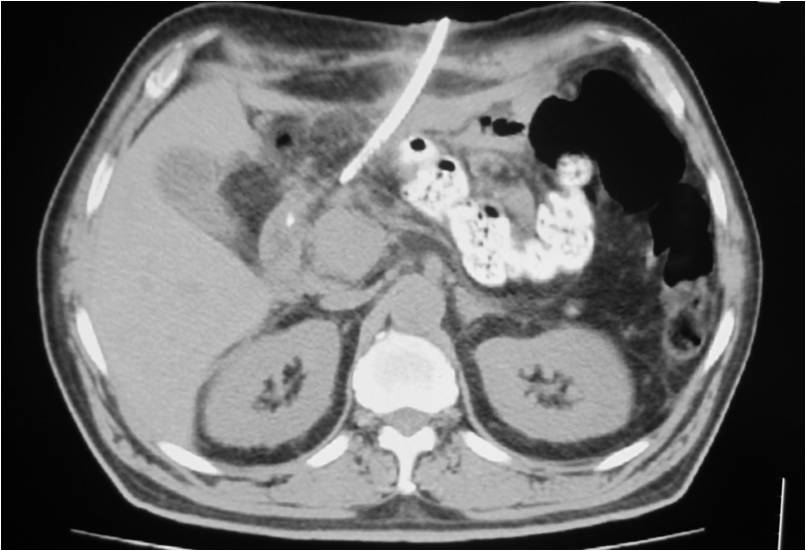

- Successful placement in sub-hepatic abscess post right hemicolectomy

- Right sub diaphragmatic abscess post right hemicolectomy

- Successful drainage